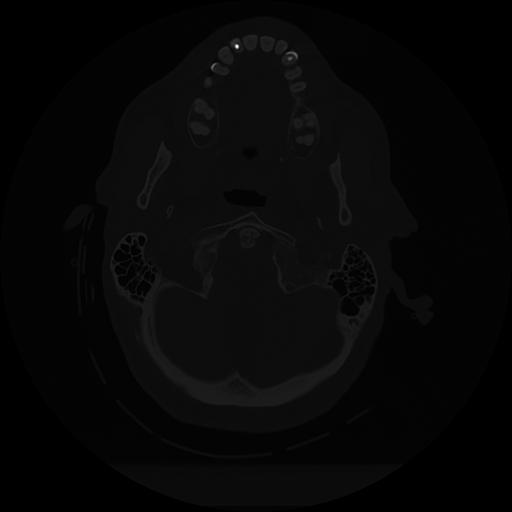

11 HUESO,,Axial,2.0,HUESO,,